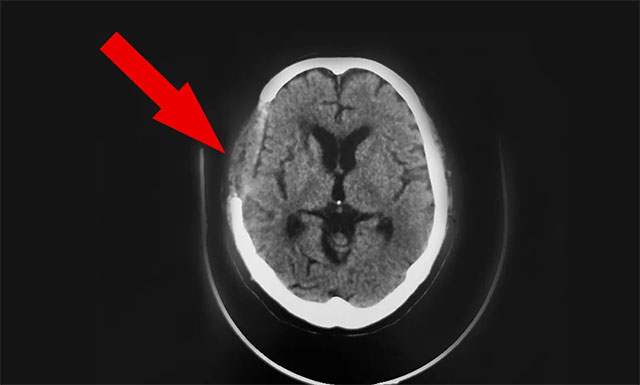

手術(shù)后一天,患者胡某蘇醒,頭腦清醒,并能下地走動(dòng)。

▲ 手術(shù)后

10月8日,雙節(jié)的最后一天,患者神志清,精神佳,眼球各向活動(dòng)好,伸舌居中,張口、鼓腮、吹起動(dòng)作可,雙肺呼吸音清,四肢肌張力正常,雙側(cè)巴氏征未引出;诨颊呋謴(fù)可,予以辦理出院。